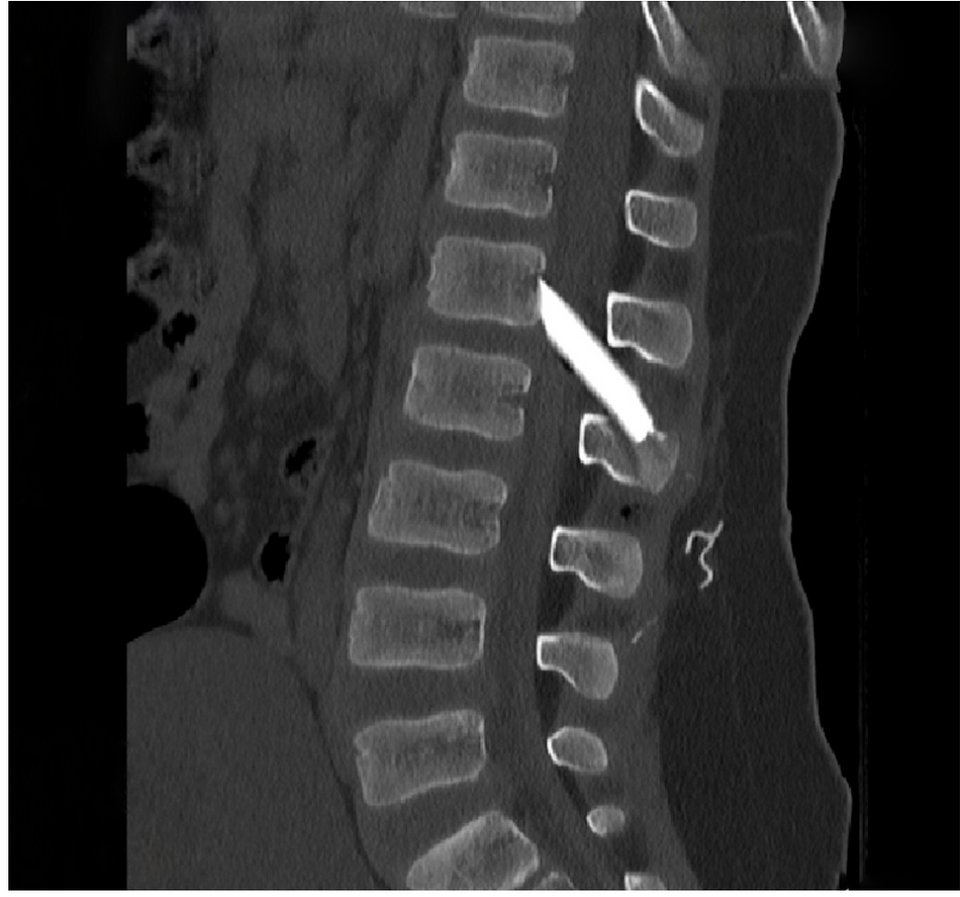

Οι μαγνητικές και αξονικές τομογραφίες πραγματοποιήθηκαν άμεσα, επιβεβαιώνοντας τις αρχικές υποψίες: δύο μεγάλα κομμάτια γυαλιού είχαν ενσφηνωθεί στη σπονδυλική στήλη, εισχωρώντας εντός του σπονδυλικού σωλήνα σχίζοντας την ιππουρίδα και την μήνιγγα που την περιβάλλει.

Ακολούθησε άμεση εισαγωγή του παιδιού στο χειρουργείο, όπου με πολύ προσεκτικούς χειρισμούς και τη χρήση προηγμένου εξοπλισμού, όπως το σύστημα χειρουργικής πλοήγησης, πραγματοποιήθηκε επιτυχής αφαίρεση όλων των κομματιών γυαλιού μετά από ένα πολύωρο και απαιτητικό χειρουργείο.